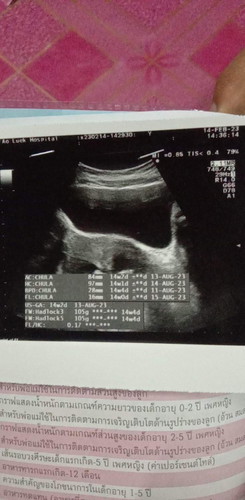

ตอนซาวด์14w2dหมอบอกน้องตัวเล็กมากหนักแค่105กรัมเอง..ตอนนี้แม่เข้า4เดือนแล้วค่ะแต่น้ำหนักตัวไม่ขึ้นเลยแต่กินข้าวได้ปกติไม่มีอาการเเพ้ท้องกินนมบำรุงตลอดต้องทำยังไงน้ำหนักถึงจะขึ้นค่ะกลัวน้องเกิดมาแล้วตัวเล็ก..ท้องแรกค่ะขอคำแนะนำแม่ๆหน่อย#ขอบคุณล่วงหน้านะคะ #ท้องแรกคะ